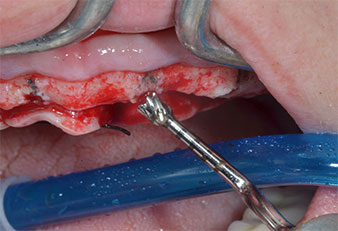

Para marcar las posiciones del implante y realizar la preparación piloto, se utilizó un inserto piezoeléctrico (Piezomed I1) con revestimiento de diamante y forma de llama (figura 3). Se tomaron precauciones para realizar movimientos hacia arriba y hacia abajo, con una potencia reducida, una irrigación completa y una baja presión (por debajo de 300 g). A continuación, se aplicó un inserto piloto (Piezomed I2A/I2P) para aumentar el diámetro inicial de 2 mm de los sitios de implante (figura 4), seguido de un inserto de 3 mm (Fig. 5).

En el caso que nos ocupa, no se utilizaron los insertos Z25P ni Z35P debido a la existencia de un hueso posterior relativamente blando, que se trató sin problemas con el I3A/I3P.